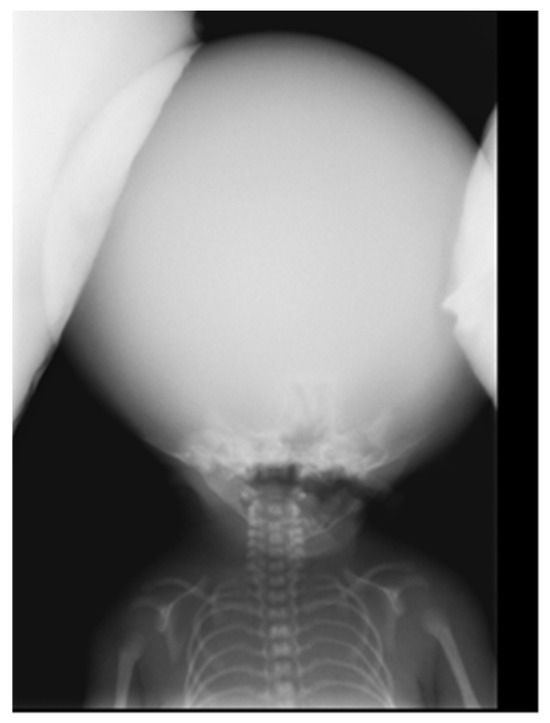

The intricacies of disorders of the oral cavity, head, and neck present clinicians with significant challenges, necessitating a multidisciplinary approach to achieve accurate diagnosis and effective therapeutic strategies. This Special Issue aims to explore the spectrum of complex cases encountered in these anatomical regions, encompassing diverse etiologies, diagnostic dilemmas, and therapeutic interventions. By delving into nuanced clinical scenarios, this collection seeks to foster a deeper understanding of the complexities that are inherent to managing conditions ranging from oral cancers and maxillofacial trauma to rare pathologies and treatment-resistant diseases. Through case presentations, innovative diagnostic techniques, therapeutic modalities, and outcome assessments, this Special Issue endeavors to advance our knowledge and enhance clinical practice regarding disorders of the oral cavity, head, neck. Contributions from clinicians, researchers, and allied healthcare professionals are invited, in order to enrich this exploration and contribute to our collective effort to address the formidable challenges posed by these interlinked clinical scenarios. For this Special Issue, we would particularly like to publish research articles and comprehensive reviews.